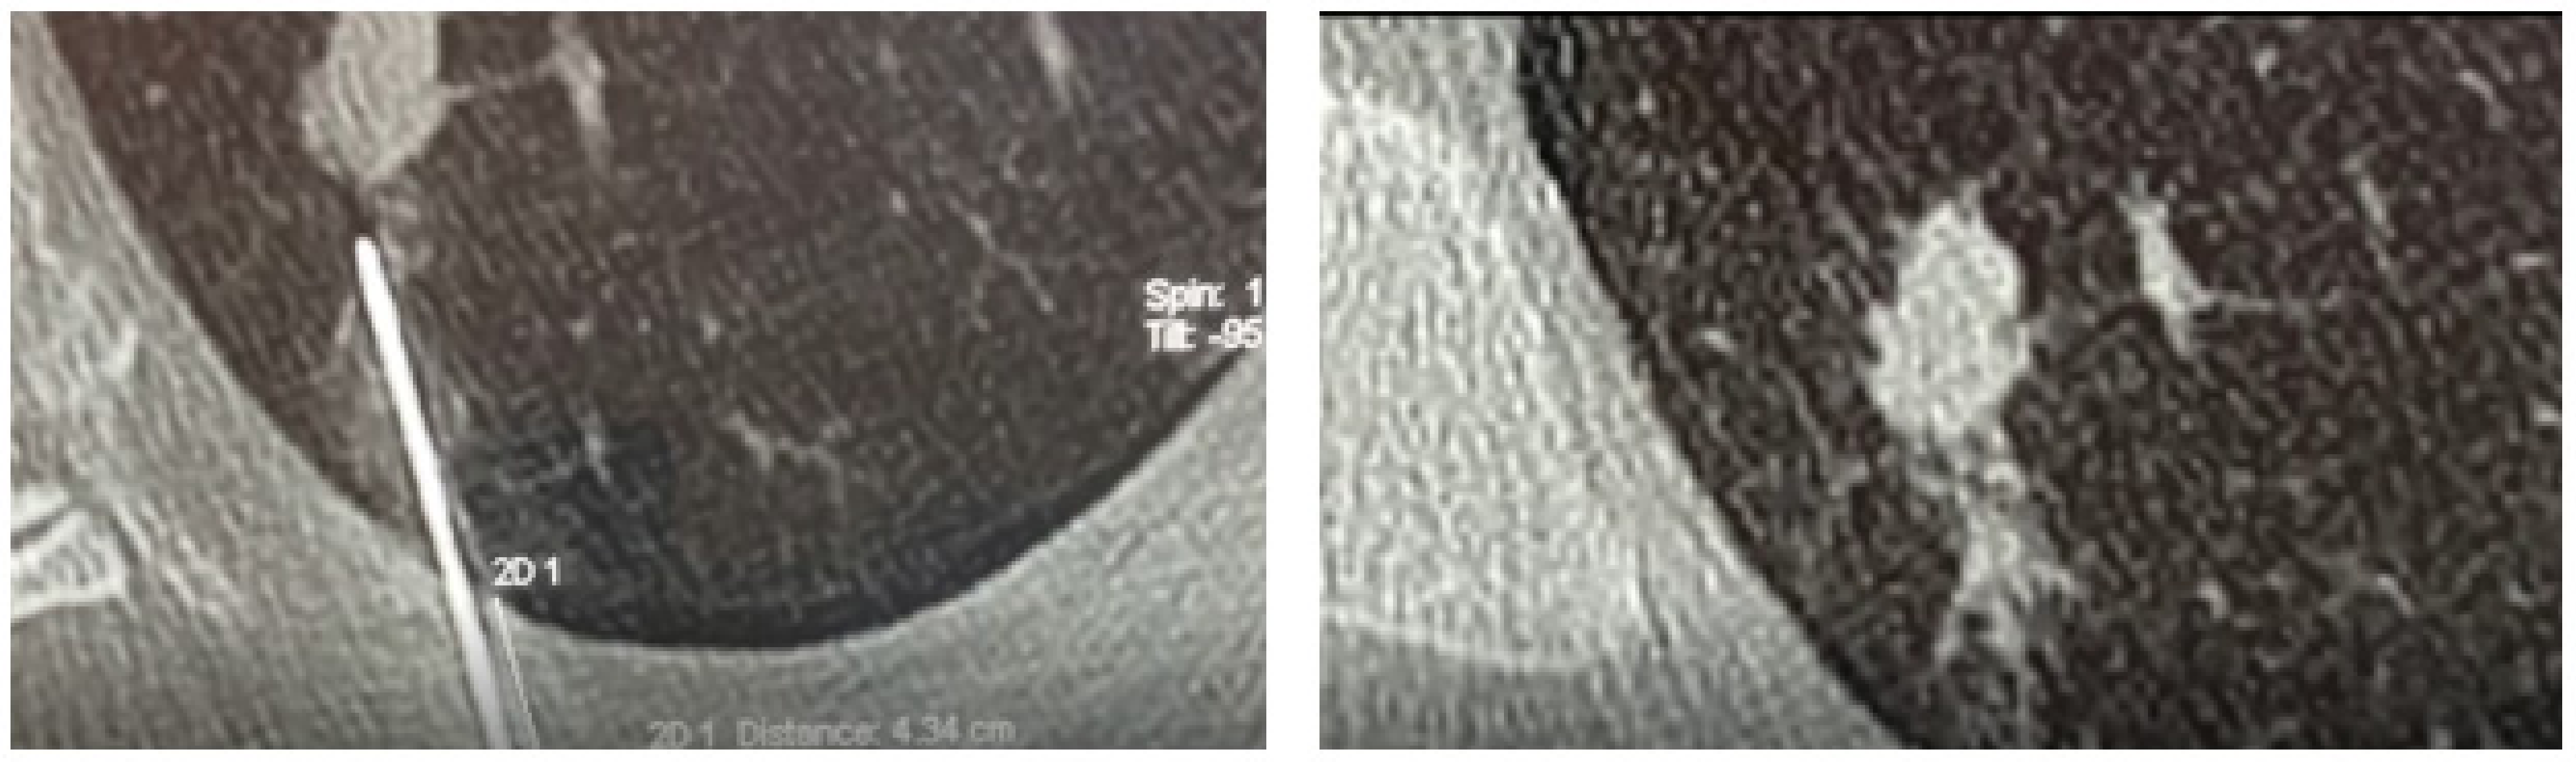

Once the low-dose CT examination was carried out, the images were sent to the navigation system in DICOM format. At this point, using the guidance of the navigation system in spontaneous breathing, since the navigator is equipped with a correction of the respiratory movements, a 19 G needle was introduced at the level of the known target. The Biosentry system was then released according to the manufacturer’s instructions (Figure 1). A control CT scan was performed at the end of the procedure to detect any complications (e.g., pneumothorax, pleural effusion, or bleeding). Though the plug is not radiopaque, it can sometimes be seen on the control CT scan (Figure 2).

Figure 2. A CT scan showing the plug deployment.